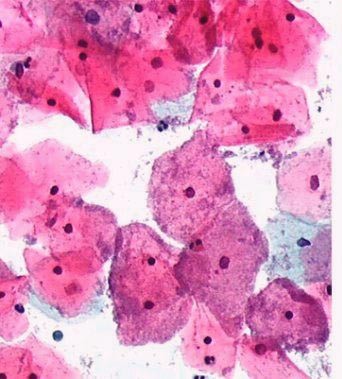

Папилломавирусная инфекция

Передается при любом интимном контакте где наблюдается соприкосновение слизистых оболочек. Вызывает семейство вирусов папилломы человека. Риск заражения зависит от возраста и состояния иммунитета. У хорошо защищенных людей данный вирус не приживается.

Как распознать:

— Родинка в виде гриба на тонкой ножке располагается внутри и снаружи половых органов.

— Наблюдаются выделения с примесью крови после интимной близости.